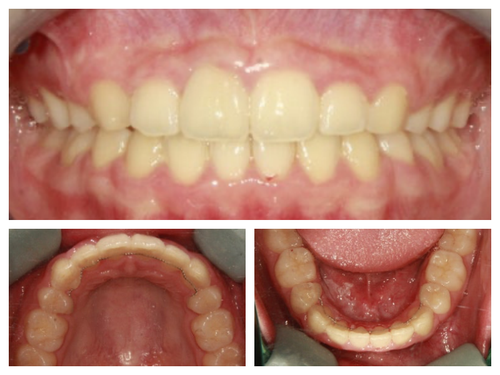

사실 골격적인 비대칭이 심해서 교정이 끝나도 비대칭이 남겠지만 돌출이 개선되면 훨씬 예뻐질것이기에 과감히 발치를 하고 좌,우 최대한 중심선을 맞추면서 교정을 끝낸 케이스

입이 들어가서 예뻐진 것 뿐아니라 사진을 찍으면 두드러지던 비대칭도 많이 줄어들었다.

네 개의 소구치를 발치하고 교정을 시작했다.

돌출입 교정을 통해 입술의 모습이 많이 바뀌니 잇몸 노출량도 훨씬 줄어서 웃을때 신경이 더 쓰인다고...